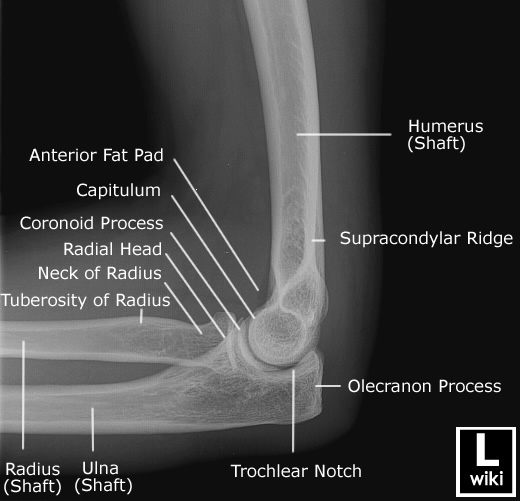

This is what we are looking at

Image source

And what does this translate to? (sorry this one is flipped around)

As you can see, even understanding a simple elbow X-Ray requires a fairly in-depth understanding of bony anatomy.

Now we won't cover the anatomy of every bone and joint today, but if you're interested in peeking at a mate's, family members or your own X-Ray next time it might be a good idea to have a quick google of the region you're going to be looking at.